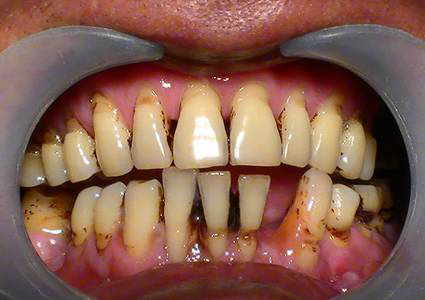

牙齦周圍菌斑、牙結(jié)石大量堆積,細(xì)菌大肆滋生刺激牙齦,引發(fā)炎癥,導(dǎo)致牙齦萎縮、牙齒松動(dòng)、移位等問(wèn)題,牙齒看上去就感覺(jué)像變長(zhǎng)了。

成年人多少都患有牙周疾病,但因進(jìn)展緩慢常常忽略,發(fā)現(xiàn)問(wèn)題時(shí)已到“牙周病末期”了,雖然可以通過(guò)牙周治療去除牙結(jié)石,緩解炎癥,但萎縮的牙齦卻再也找不回來(lái)了。

很多人不及時(shí)治療,都會(huì)發(fā)展成下面這種情況↓

預(yù)防:防止牙周病_好的辦法就是每半年到1年定期洗牙一次,洗牙是有效去除牙結(jié)石的唯一辦法。

治療:如果已經(jīng)患了牙齦萎縮的朋友,需要盡早進(jìn)行牙周刮治,將牙齦邊的牙結(jié)石清除干凈,雖然之前的牙齦很難救回來(lái)了,但防止它繼續(xù)萎縮下去也是非常必要的。